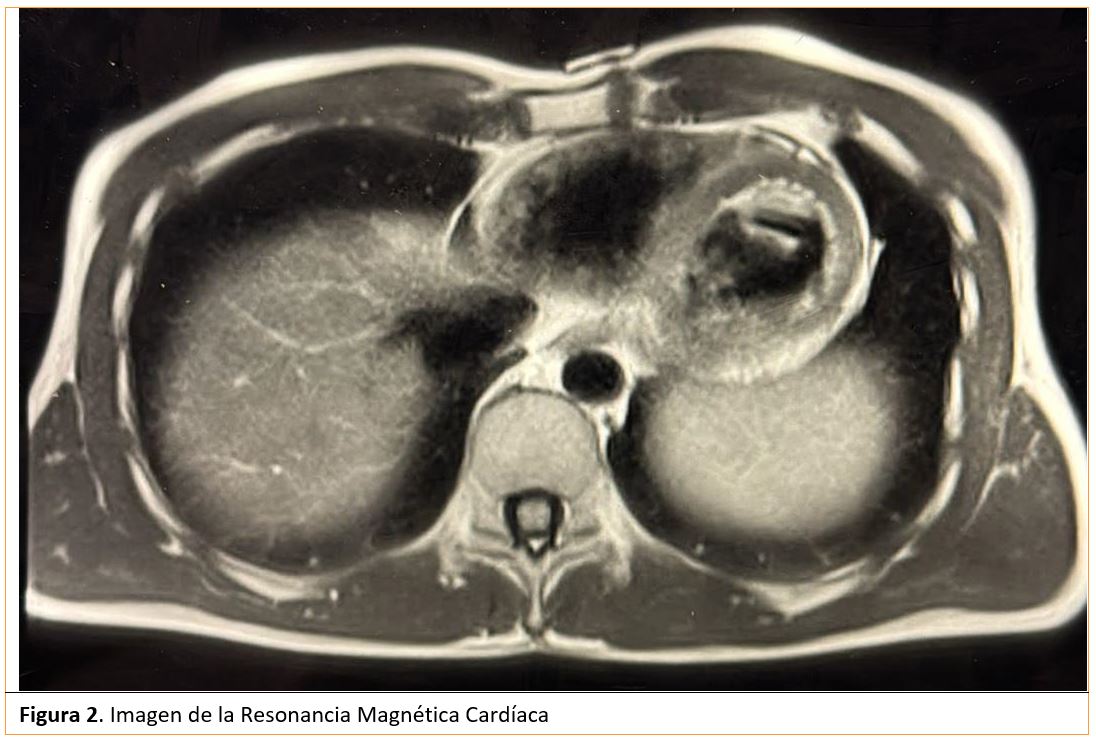

Evolución: paciente ingresa a cargo de Cardiología donde se realiza una Resonancia Magnética Cardiaca (RMC) urgente cuyo informe reporta: Fibrosis miocárdica extensa circunferencial afectando a epicardio y medio miocardio desde la zona más basal a la más apical del Ventrículo Izquierdo. Posible realce tardío también afectando el Ventrículo Derecho en su región apical (figura 2).